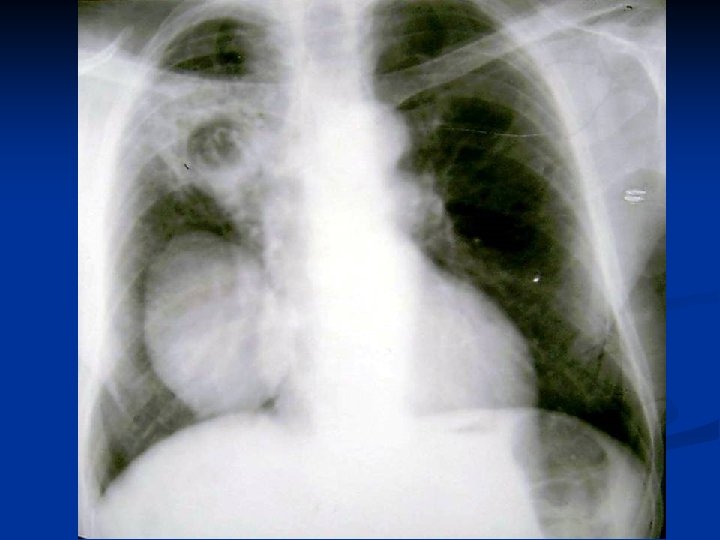

Caracteristici generale n n n Boala parazitara determinata de Taenia echinococcus granulosus. Descrisa inca de pe vremea lui Hipocrat si a lui Galen. Termenul de “chist hidatic” utilizat de Rudolphi in 1908. Localizarea pulmonara este a doua ca frecventa dupa cea hepatica. Boala cu distributie endemica in regiunea mediteraneana, Orientul Mijlociu, Australia, Noua Zeelanda, America de Sud.

Metode de diagnosticare